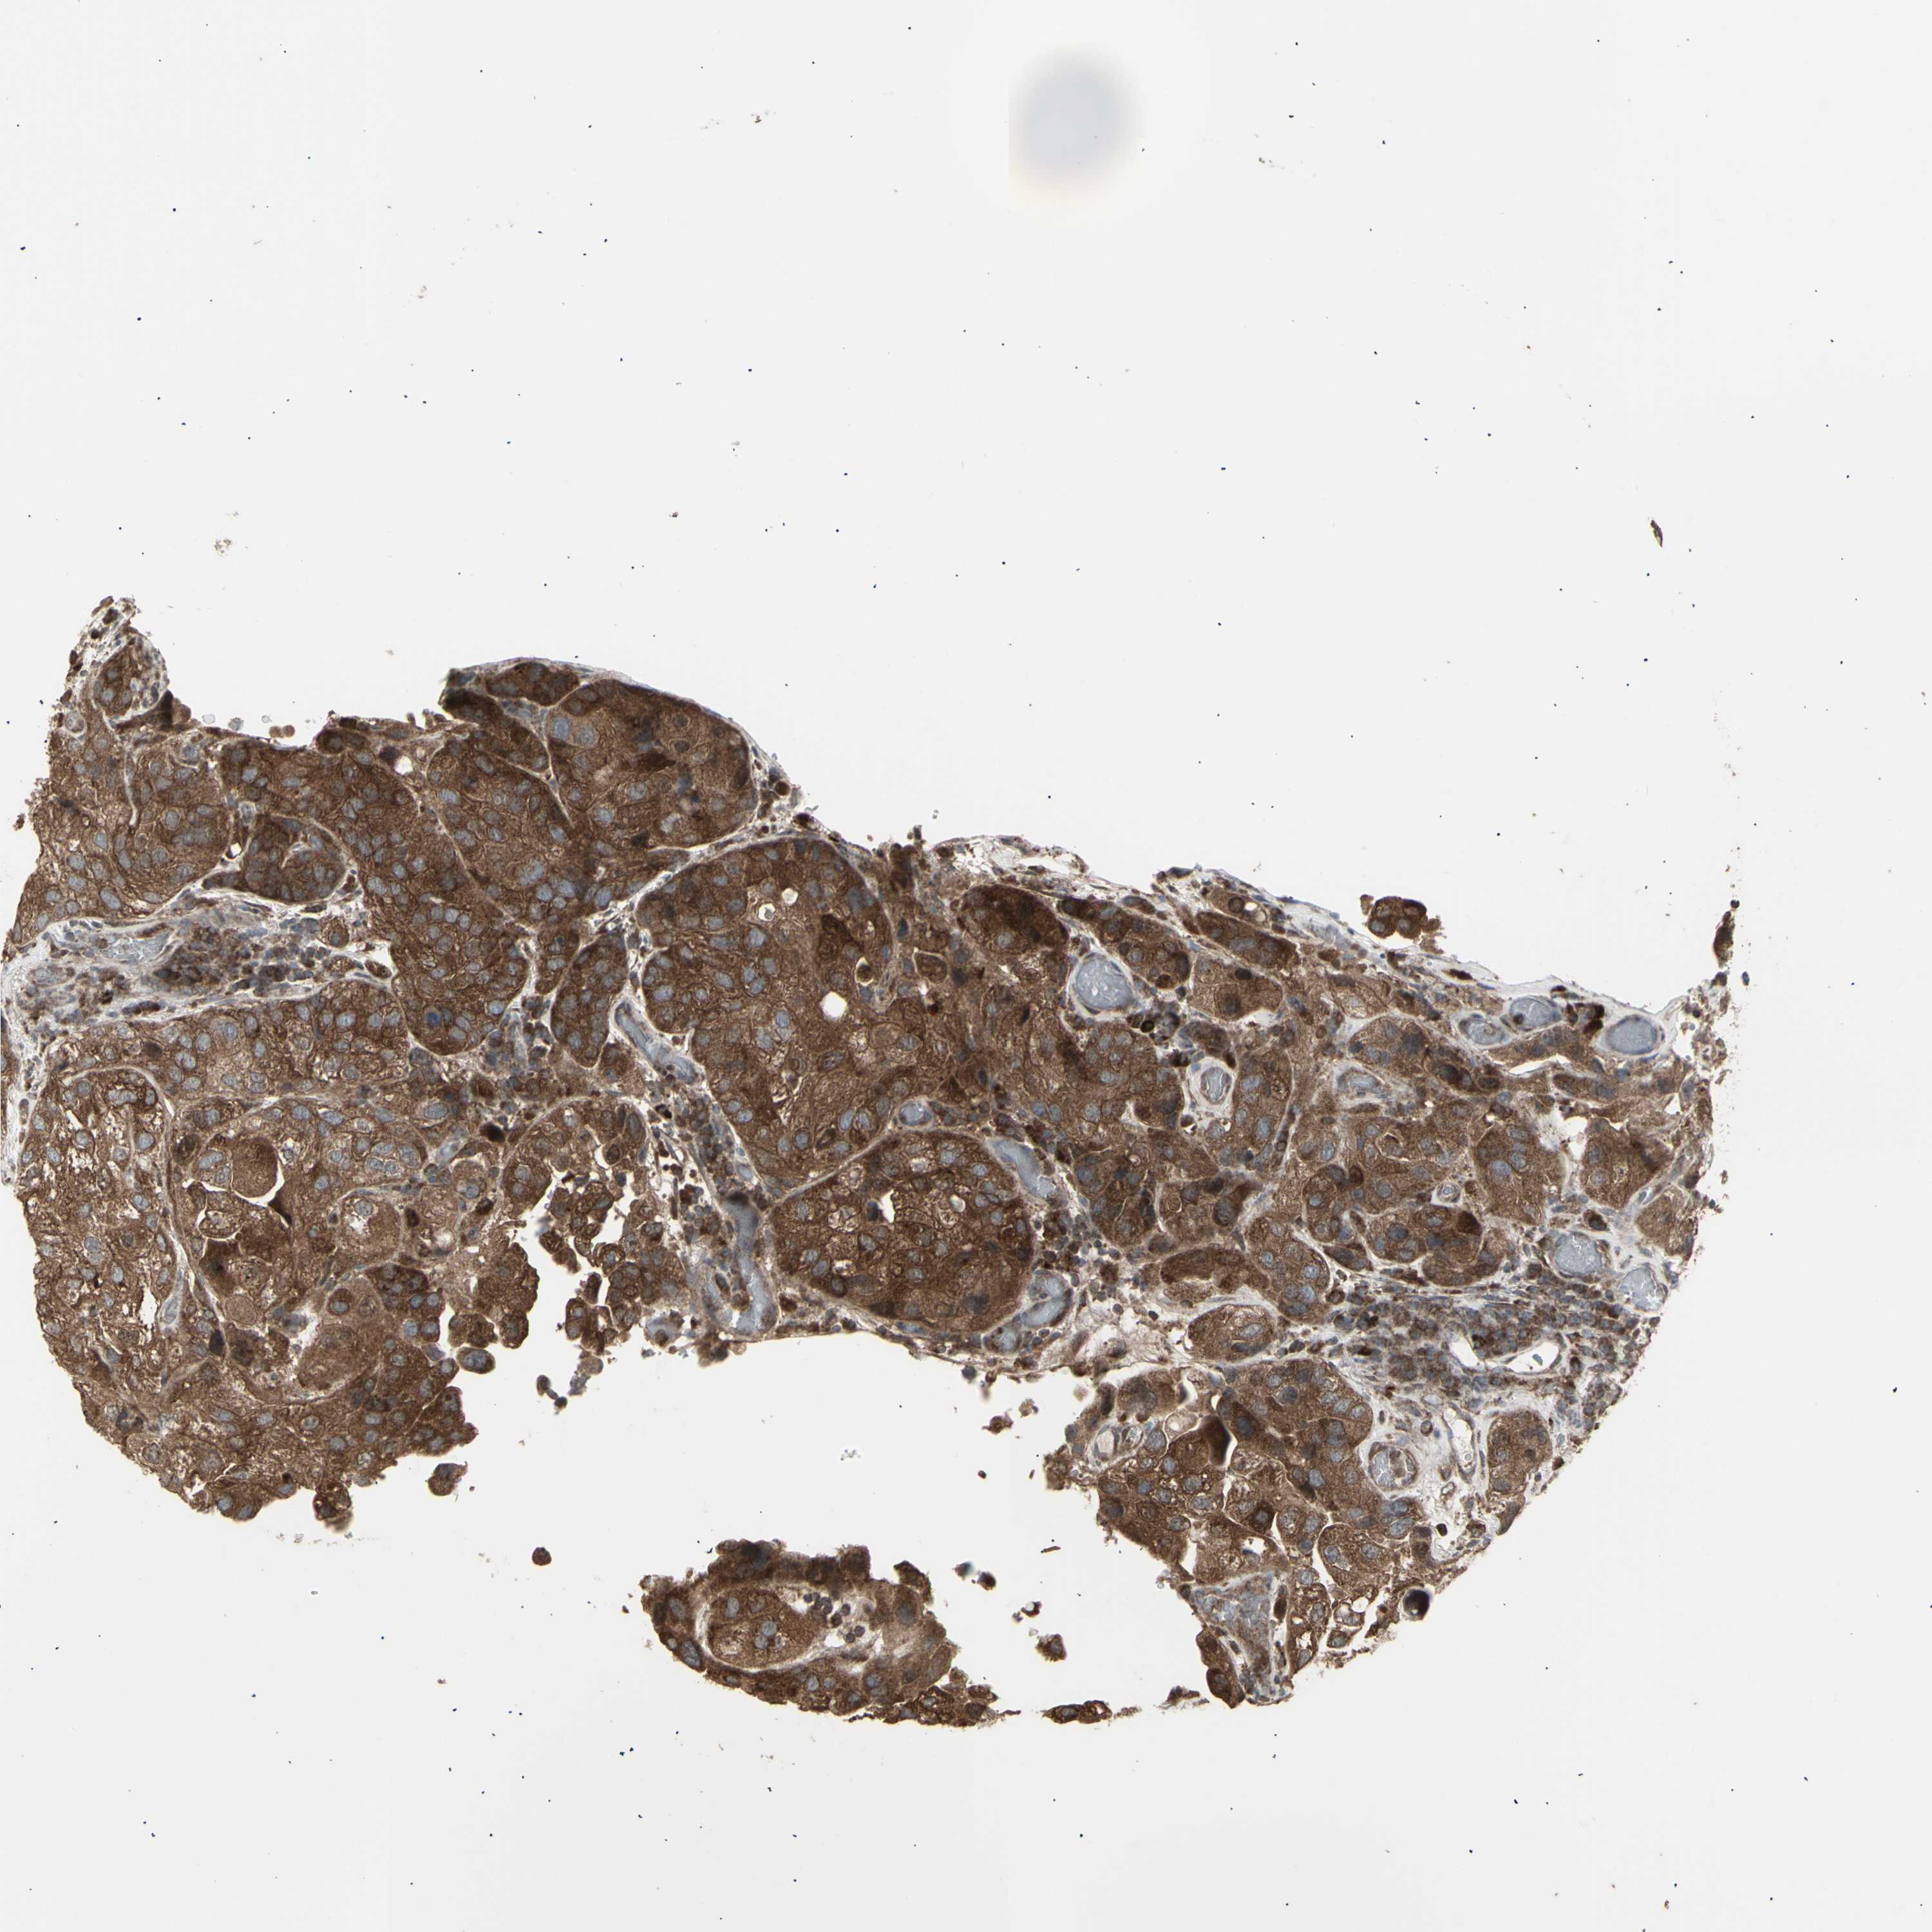

UROTHELIAL CANCER - Protein expressioni

A mouse-over function shows sample information and annotation data. Click on an image to view it in a full screen mode. Samples can be filtered based on level of antibody staining by selecting one or several of the following categories: high, medium, low and not detected. The assay and annotation is described here.

Note that samples used for immunohistochemistry by the Human Protein Atlas do not correspond to samples in the TCGA dataset.

Antibody stainingi

Antibody staining in the annotated cell types in the current human tissue is reported as not detected, low, medium, or high, based on conventional immunohistochemistry profiling in selected tissues. This score is based on the combination of the staining intensity and fraction of stained cells.

Each image is clickable and will lead to virtual microscopy that enables deeper exploration of all samples and also displays staining intensity scores, fraction scores and subcellular localization as well as patient and tissue information for each sample.

Antibody HPA002633

Antibody HPA046758

Antibody CAB010906

Staining

High

Medium

Low

Not detected

Intensity

Strong

Moderate

Weak

Negative

Quantity

>75%

75%-25%

<25%

None

Location

Nuclear

Cytoplasmic/membranous

Cytoplasmic/membranous,nuclear

Urothelial carcinoma, High grade

Urothelial carcinoma, Low grade